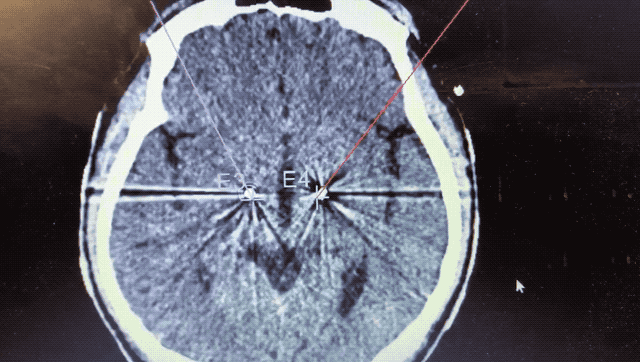

順利檢測到典型的核團信號后,再次植入刺激電極到相應(yīng)位置,測試后即可完成單側(cè)的電極植入。對側(cè)只需借助機器人再次定位,并將檢測電極、刺激電極依次植入,最后,還需將刺激器植入患者胸前皮下。根據(jù)術(shù)后CT顯示,本手術(shù)雙側(cè)植入電極的位置與術(shù)前規(guī)劃路徑完全吻合,患者開機后,起搏器會開始沿刺激電極向患者核團實施高頻電刺激,以減輕疾病癥狀,提高患者的生活質(zhì)量。

術(shù)后CT顯示雙側(cè)電極植入位置與規(guī)劃完全吻合